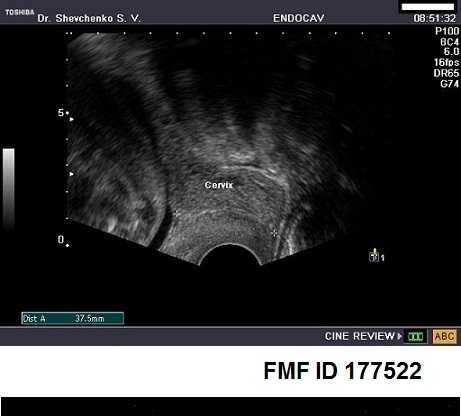

Цервікометрія – це вимірювання довжини шийки матки за допомогою ультразвукового дослідження. Така процедура дозволяє своєчасно діагностувати можливе укорочення шийки матки, яке може призвести до передчасних пологів. Розуміння цього процесу допомагає багатьом жінкам зберегти вагітність. Але що саме ми розуміємо під “нормою” в цервікометрії?

- Трансвагінальне УЗД: найбільш точний метод. Дозволяє лікарям отримати чітке уявлення про стан шийки матки. Проводиться з використанням спеціального датчика, що вставляється у вагіну.